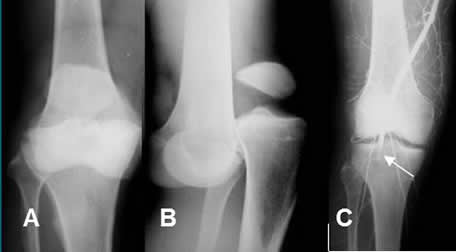

Está indicado el estudio con arteriografía, ante la sospecha o signos clínicos de lesión vascular. Igualmente por la proximidad de las fracturas a los grandes vasos y traumas penetrantes por arma blanca y bala. Ej lesiones de vasos subclavios, por fracturas complejas de clavícula o articulaciones esternoclaviculares, arteria braquial por luxación del codo o fractura del húmero, etc. (1, 3). (Fig 31 y 32).

Fig 31. Arteriografía.

A: Rx AP y B: Rx lateral. Luxación posterior de la rodilla.

C: Arteriografía. Oclusión de la arteria poplítea.